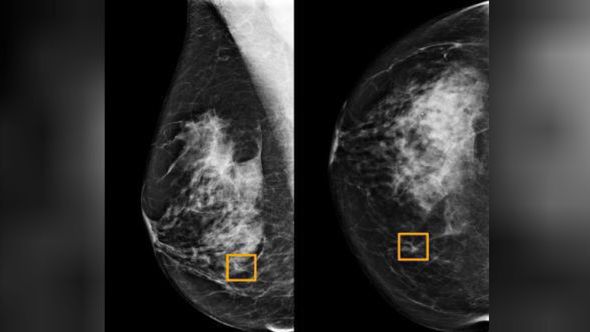

W trakcie testów sztuczna inteligencja dokonała analiz ponad 28,5 tys. mammogramów w Wielkiej Brytanii oraz z górą 3 tys. takich badań w Stanach Zjednoczonych.

Okazało się, że w USA AI zredukowała o 5,7 proc. przypadki, w których lekarze fałszywie zdiagnozowali raka piersi u pacjentek, u których w rzeczywistości ta choroba nie wystąpiła. Z kolei o 9,4 proc. zmalała liczba przypadków, w których kobiety uznane przez lekarzy za zdrowe w rzeczywistości chorowały na nowotwór piersi.

W Wielkiej Brytanii testy wykazały zmniejszenie liczby fałszywych dodatnich wyników o 1,2 proc., zaś fałszywie negatywnych – o 2,7 proc. Dysproporcje w wynikach osiągniętych w USA i Wielkiej Brytanii mają wynikać z tego, że w tym drugim kraju analizy testów mammograficznych dokonywane przez lekarzy są systemowo bardziej precyzyjne niż w Stanach.